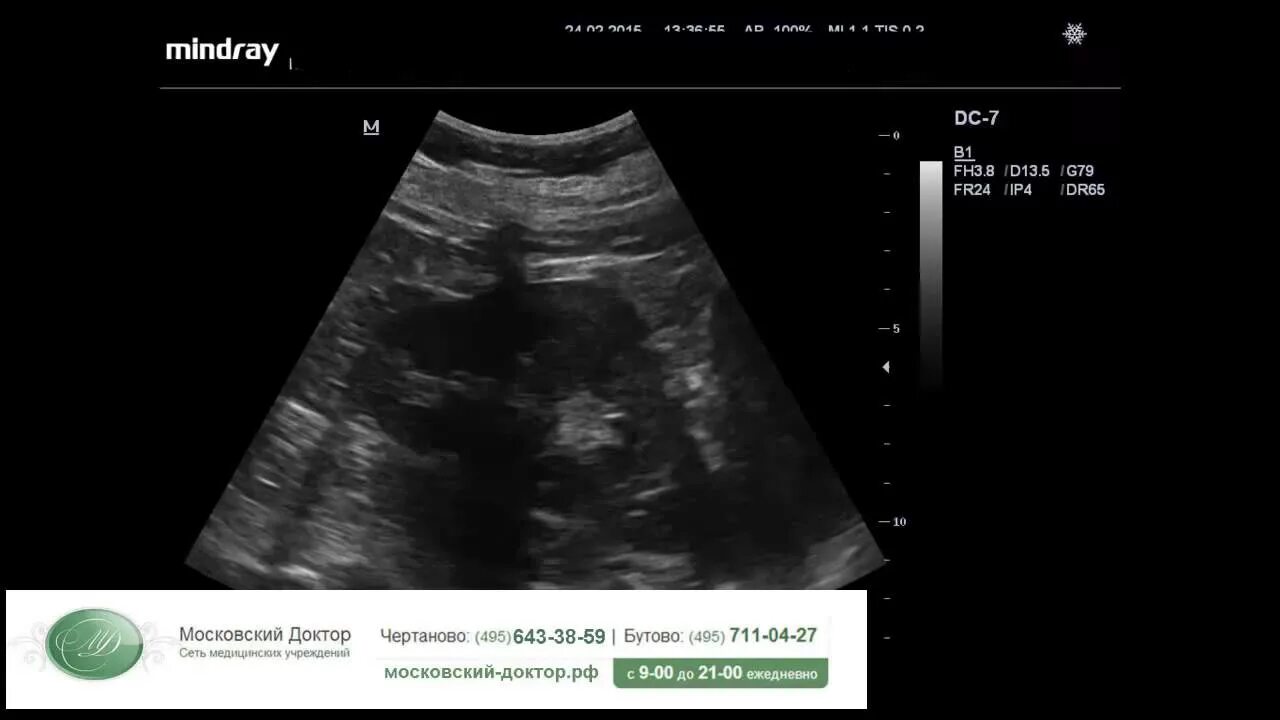

Узи желчного пузыря подготовка к процедуре